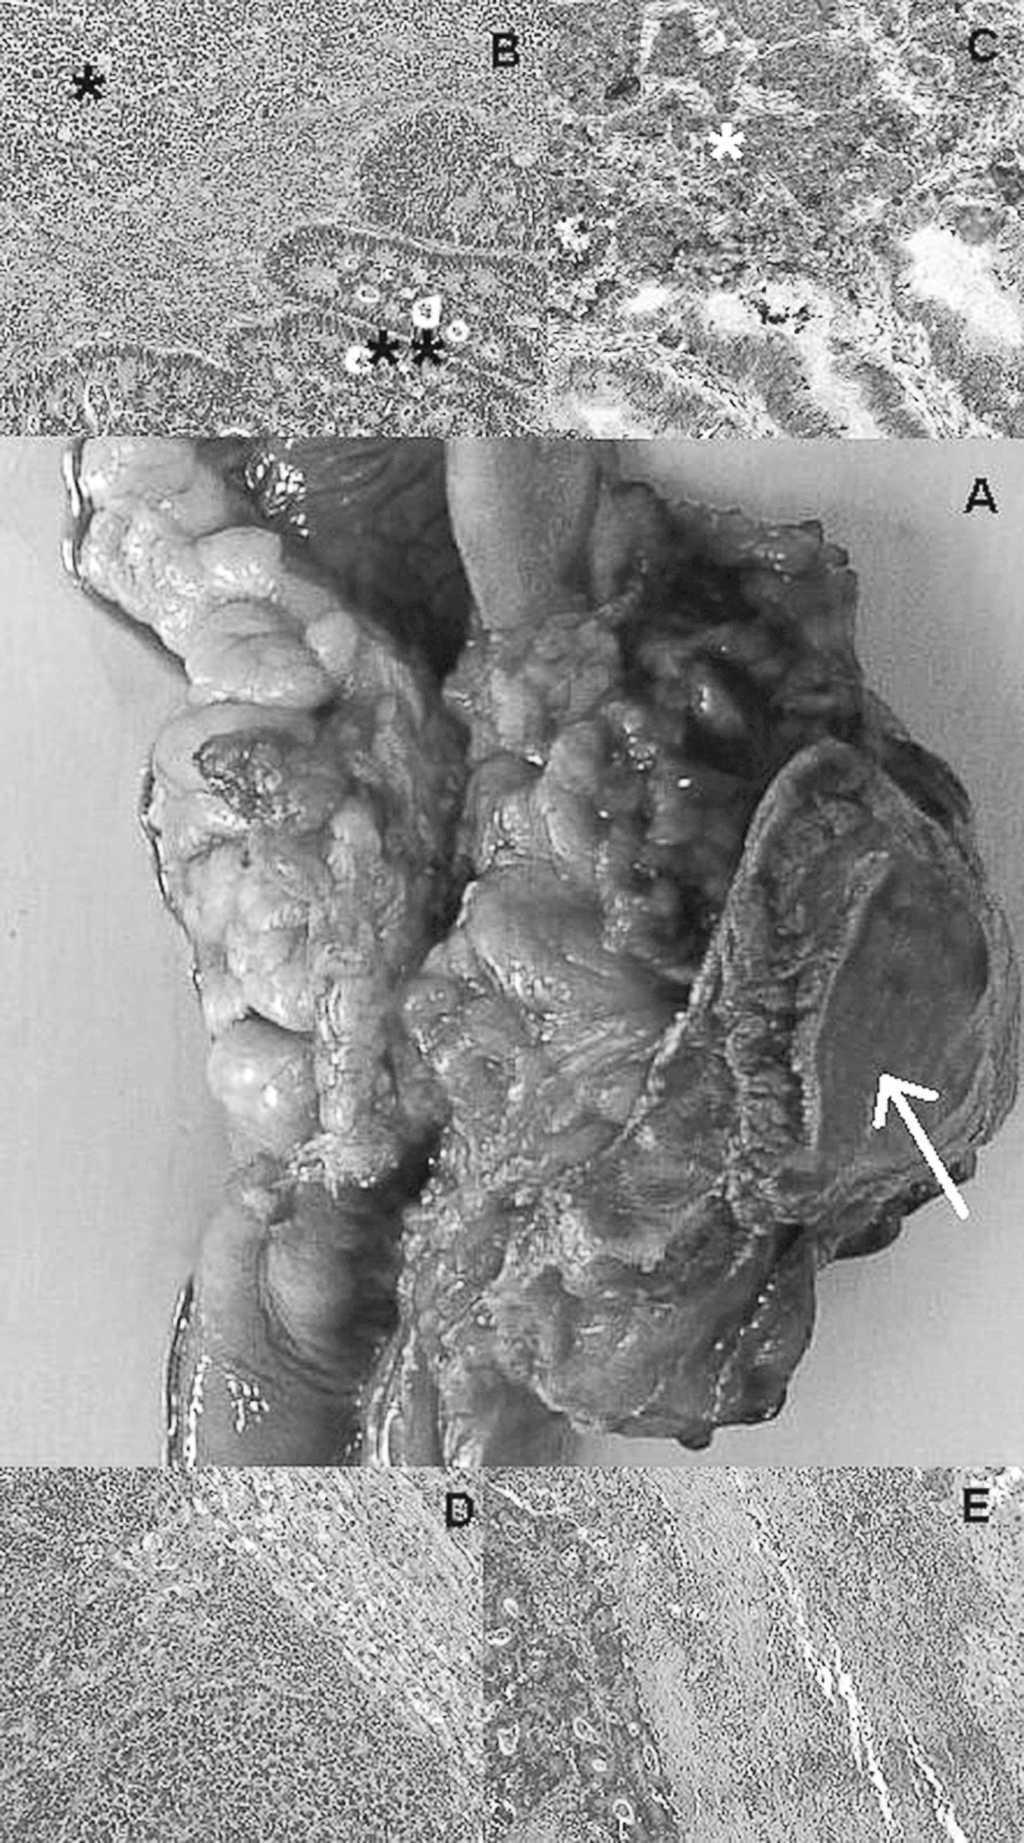

La paciente fue intervenida quirúrgicamente el 1 de marzo de 2006, y durante la cirugía se encontró un tumor en el ángulo esplénico con deterioro de la serosa, de aproximadamente 7 cm, adherido al diafragma (fig. 2A). Además, un absceso peritumoral de aproximadamente 50 ml y múltiples adenopatías de aspecto neoplásico. La exploración hepática, manual y ecográfica, mostró 2 lesiones de aspecto tumoral: una en el segmento II y otra en el segmento V. En el resto de la cavidad abdominal no se observaron otras lesiones tumorales. Se practicó una hemicolectomía derecha ampliada con resección de un segmento de diafragma, ileosigmoidoanastomosis y resección de ambas metástasis hepáticas. La paciente tuvo una evolución postoperatoria sin complicaciones. El estudio anatomopatológico de la pieza quirúrgica confirmó un cáncer de colon ulcerado, deprimido, anular y estenosante de 8 x 7,5 x 5 cm, que infiltraba el tejido pericolónico. El estudio microscópico mostró un adenocarcinoma tubular, moderadamente diferenciado, con extensas áreas de carcinoma neuroendocrino poco diferenciado, que presentaba infiltración venosa y perineural (fig. 2B). El estudio inmunohistoquímico fue positivo en el componente neuroendocrino para sinaptofisina y negativo para cromogramina y enolasa. Además se observaron metástasis en 25 de 28 linfonodos (grupo pericolónico 25/26, grupo principal 0/2), 5 metástasis nodulares y 3 metástasis estrelladas en el tejido adiposo pericolónico. El estudio del tejido hepático mostró 2 metástasis de adenocarcinoma tubular moderadamente diferenciado con áreas de carcinoma neuroendocrino poco diferenciado (fig. 2C). La primera de 2,5 x 2 x 2 cm, ubicada en el segmento V, fue negativa en el estudio para pancitoqueratinas (AE1/AE3) y CD-45 (antígeno leucocitario común). La segunda de 1,5 x 1,5 x 1 cm estaba ubicada en el segmento II. Todos los bordes quirúrgicos (tumor primario y metástasis) fueron negativos para tumor.

Fig. 2. A: pieza operatoria que muestra el tumor en el ángulo esplénico del colon y que incluye un segmento de diafragma (flecha continua). B: estudio microscópico (tinción hematoxilina-eosina, x40); tumor de colon compuesto, en el extremo superior izquierdo (*) se observa un tumor sólido de células pequeñas, redondas y azules. En el extremo inferior derecho (**), se identifica un adenocarcinoma tubular moderadamente diferenciado. C: estudio inmunohistoquímico con anticuerpos monoclonales contra sinaptofisina que revela inmunorreacción positiva intensa en las células tumorales correspondientes al tumor sólido (*) y ausencia de reactividad en el adenocarcinoma tubular, confirmando la estirpe neuroendocrina del primero. D: metástasis hepática de tumor compuesto (carcinoma neuroendocrino) (hematoxilina-eosina, x10). E: metástasis hepática de adenocarcinoma tubular moderadamente diferenciado (hematoxilina-eosina, x10).